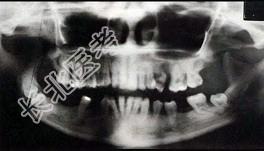

- 1、最为合理的临床诊断为 ( )